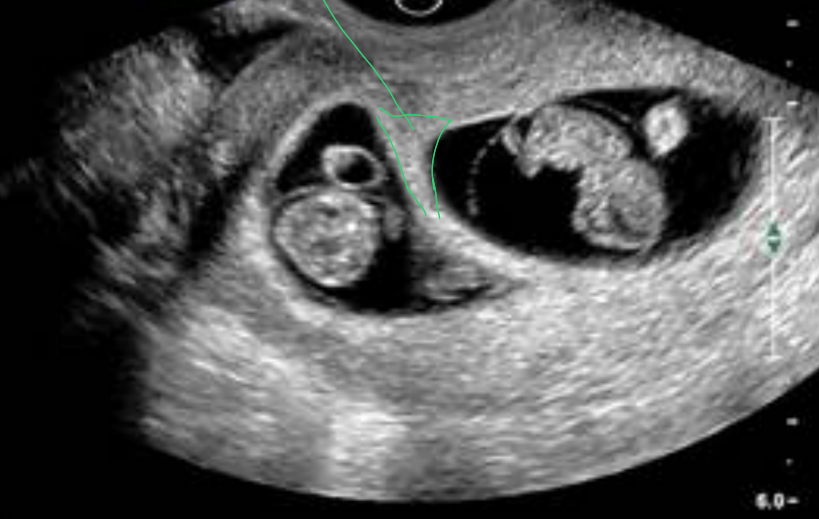

Qual a coriônicidade desta gemelaridade?

Trata-se de uma gestação dicoriônica, devido ao espessamento da parede, também conhecido de sinal Lambda